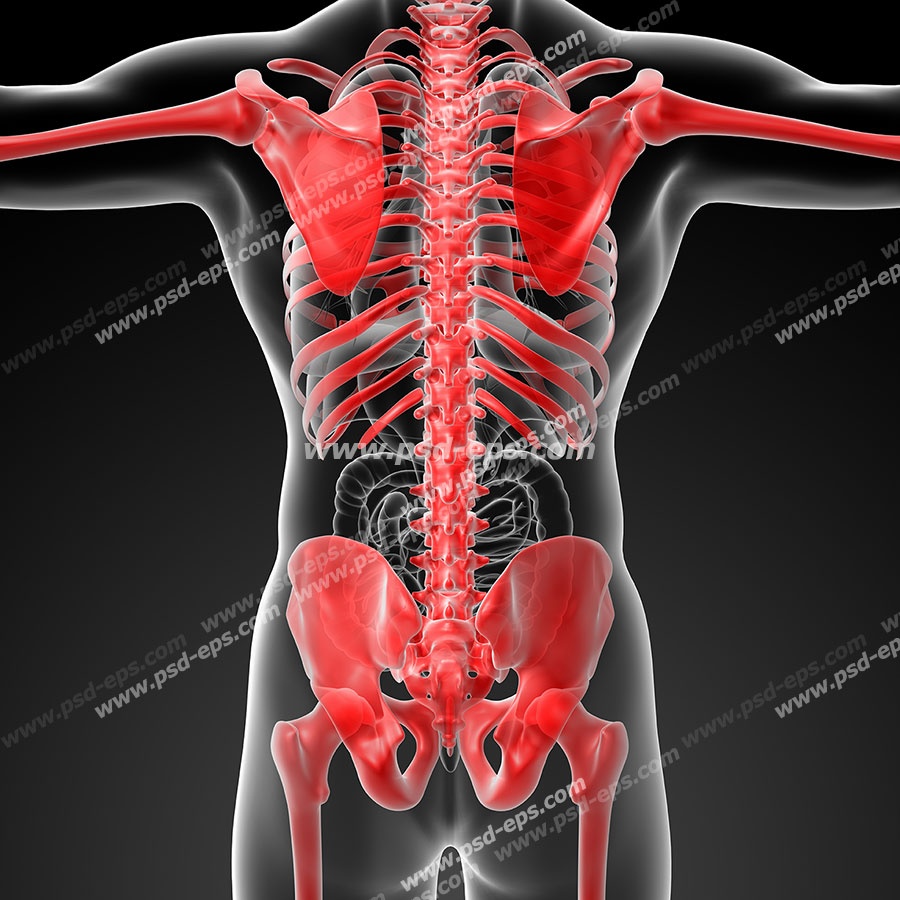

عکس اسکلت بدن انسان با کیفیت. عکس اسکلت عکس اسکلت برای پروفایل عکس اسکلت انسان عکس اسکلت خفن عکس اسکلت بدن انسان با کیفیت عکس اسکلت بدن انسان عکس اسکلت ترسناک عکس اسکلت فانتزی عکس اسکلت فانتزی دخترانه پرچم عکس اسکلت. عکس با کیفیت اسکلت داخلی انسان و درد و گرفتگی در ناحیه استخوان زانو ویژه استفاده در امور تبلیغاتی و تجاری طراحی کاتالوگ بروشور و تراکت با موضوع پزشکی فیزیوتراپی ارتوپد دکتر روماتیسم فیریوتراپ طب فیزیکی. عکس اسکلت بدن انسان زن و مرد آناتومی ساتین 16 سپتامبر 2017. اسکلت داربست بدن است تمام قسمت های بدن روی اسکلت قرارگرفته اند بدن انسان از ۲۰۶ قطعه استخوان تشکیل شده است این استخوان ها طوری با نظم کنار هم قرار گرفته اند که انسان را قادر می سازد حرکات دقیقی داشته باشد.

اسکلت جمجمه و گردن انسان ستون فقرات آناتومی اسکلت جمجمه و گردن انسان ستون فقرات آناتومی تصویر با کیفیت را از لینک زیر می توانید دانلود کنید. ۱ مطلب با کلمه ی کلیدی عکس اسکلت بدن انسان با کیفیت ثبت شده است گالری نسیم جدید ترین و با کیفیت ترین عکس های مناسبتی. عکس با کیفیت آناتومی اسکلت بدن انسان و درد و دیسک در قسمت مهره های ستون فقرات کمر ویژه استفاده در امور تبلیغاتی و تجاری طراحی کاتالوگ بروشور و تراکت با موضوع بیمارستان ها و کلینیک ها و درمانگاه ها و مطب ها پزشکان و.